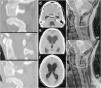

Hydrocephalus, an extremely rare complication of craniocervical junction injuries, is postulated to result from compression of the fourth ventricular cerebrospinal fluid (CSF) outlets by fractured and displaced bone fragments, a swollen upper spinal cord or adhesions formed after a traumatic subarachnoid haemorrhage. We present the case of a 21-year-old woman for whom an injury to the cervical spine complicated by a type I atlanto-occipital dislocation contributed to the development of non-communicating hydrocephalus. The hydrocephalus was probably a consequence of impaired CSF circulation at the fourth ventricular outlets (the foramina of Luschka and Magendie), caused by post-haemorrhagic adhesions formed after severe injury to the craniocervical junction.